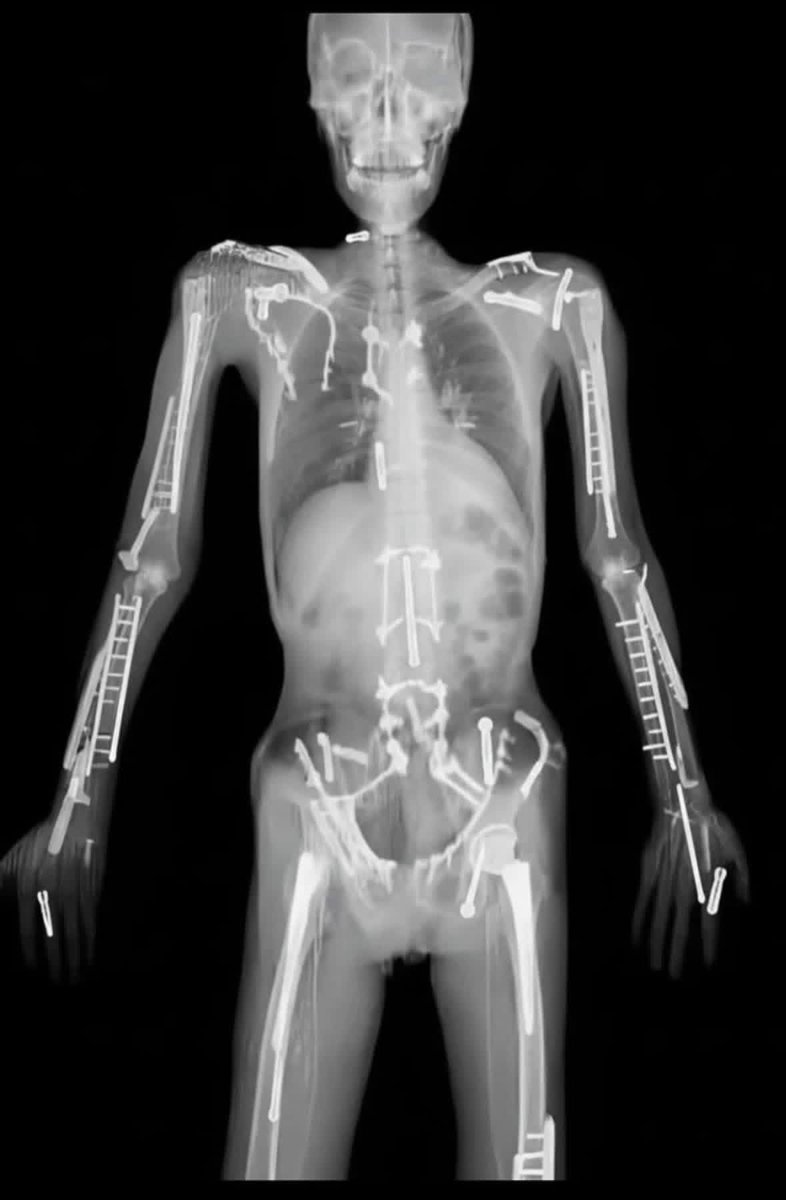

🩻 X-ray Challenge: What is the most likely diagnosis based on this X-ray? #Orthopedics #Xray #MEDHM

hemo_shk's tweet image. 🩻 X-ray Challenge:

What is the most likely diagnosis based on this X-ray?

#Orthopedics #Xray #MEDHM